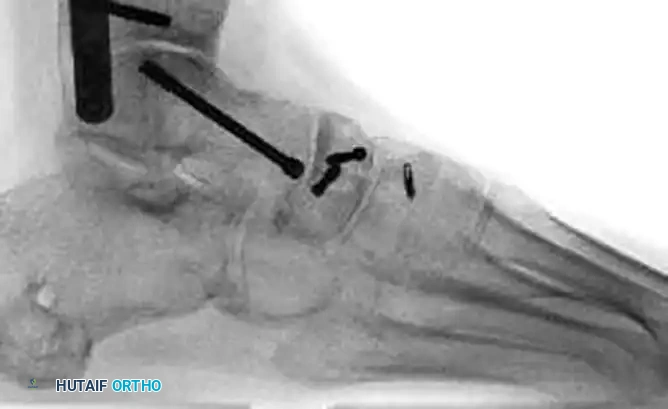

3. Reduction: The fracture is debrided of hematoma. A femoral distractor or external fixator may be temporarily applied between the talus and the medial cuneiform to restore medial column length and allow visualization of the articular surface.

For Type I and simple Type II fractures, lag screw fixation (3.5 mm or 4.0 mm partially threaded screws) directed from dorsal to plantar or lateral to medial is often sufficient.

For Type III comminuted fractures, maintaining medial column length is paramount. Temporary bridge plating or external fixation is highly recommended. A 2.7-mm or 3.5-mm reconstruction plate can be used to span the comminuted segment, extending from the talar neck to the medial cuneiform or first metatarsal.